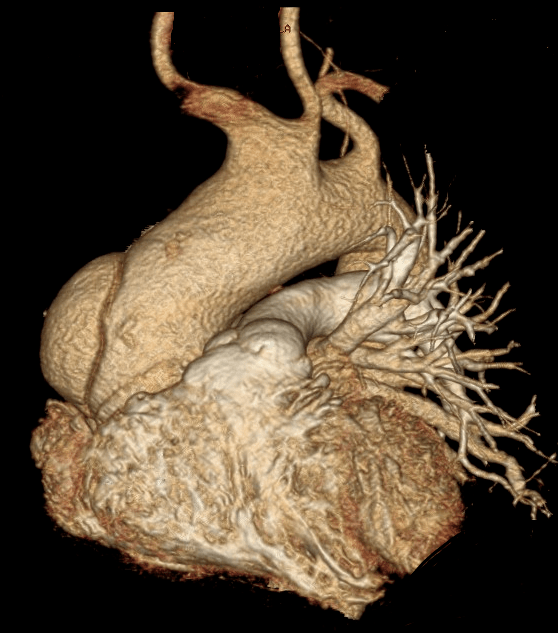

一例罕见的心血管疾病自发性冠状动脉夹层病例报告

图片尺寸510x383